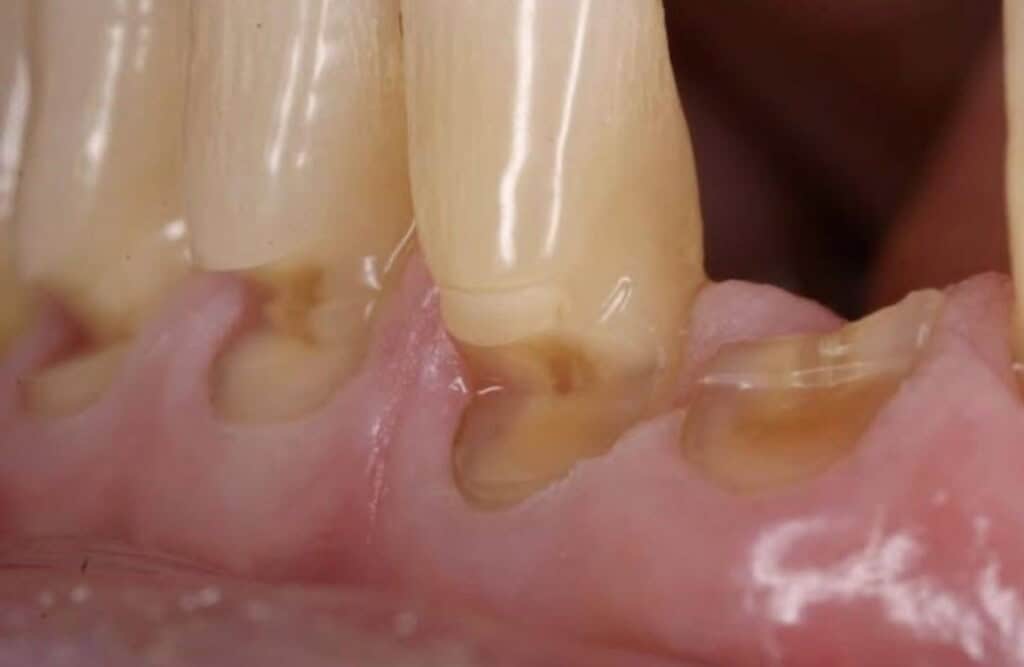

Do you notice 'tooth wear' like this on the front of your teeth? If so book in now to discuss your options to prevent tooth fracture! 01142686076 or book online via our website homepage